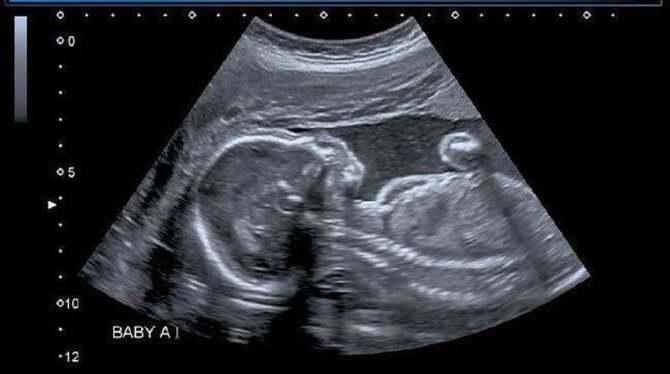

Hasil USG

Ini dia hasil USG bayi yang dikandung Nadya.

Instagram @nadyamustikarahayu ©2021 Merdeka.com

Dalam keterangan foto, wanita berhijab asal Bandung itu memberikan penjelasan mengenai kondisi bayi yang dikandungnya. Nadya bersyukur lantaran bayinya dalam kondisi sehat.

"Alhamdulillah sehat2 yaa nak. Trimakasih semua support dan doa nya yaa temen2. Alhamdulillah perjuangan promil berbuah maniss," papar Nadya di laman instagramnya.